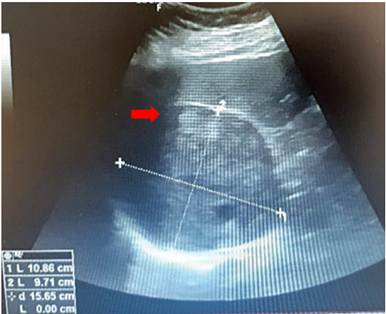

La ecografía abdominal informó una lesión sólida bien definida en espacio hepatorrenal, con ecogenicidad heterogénea, de 11 x 10 cm, en relación con tumor adrenal derecho (figura 1). La tomografía computarizada de abdomen simple y contrastada confirmó la presencia de una masa solida adrenal derecha, de 11 x 10,5 x 10,7 cm, de densidad heterogénea, con áreas centrales hipodensas por necrosis, que desplazaba y con efecto compresivo sobre la vena cava y renal derecha, y en estrecha relación con la arteria renal derecha aproximadamente a 1,8 cm de su origen, compatible con carcinoma adrenal cortical (figura 2). La resonancia nuclear magnética encontró además desplazamiento de la vena cava, hígado y riñón derecho sin invadirlos, áreas necróticas y una fuerte adherencia a la fascia pararrenal posterior derecha.